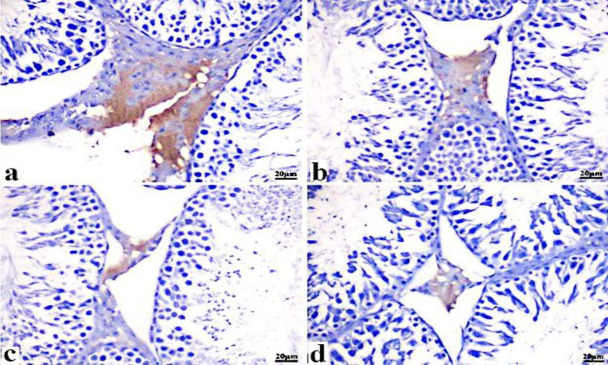

毒死蜱是一种广泛应用于农业的有机磷农药,用于控制作物的早期病害。作为男性生殖系统的内分泌干扰剂,导致生殖毒性。因此,本研究旨在探讨毒死蜱三种商业剂型对雄性大鼠雄激素受体功能和表达的潜在影响机制。本研究根据机构动物护理和使用委员会(IACUC)制定的伦理准则进行,该方案得到了开罗大学理学院的批准,批准号(CU/IF/12/23)。24只雄性Wistar大鼠平均分为4组。对照组,毒死蜱组(17.43、23.43、21.40 mg/kg)口服28 d (5 d /周)。测定血清睾酮水平,收集睾丸,用10%福尔马林缓冲液固定,进行组织病理学和免疫组织化学检查。结果表明,毒死蜱制剂可显著降低大鼠睾丸激素水平,下调雄激素受体表达。此外,在johnson评分中检测到管直径、管腔直径和生发上皮细胞厚度的显著减少。总之,暴露于三种毒死蜱制剂导致睾酮水平显著改变,雄激素受体表达减少,精子发生受损,最终导致睾丸损伤和男性不育。在评估的配方中,毒死蜱- w被确定为最有效的雄激素信号干扰物,与其他配方相比显示出更高的毒性。

Chlorpyrifos is a widely used organophosphorus pesticide for agricultural purposes to control early disease in crops. Acting as an endocrine disrupting agent for male reproductive systems which leads to reproductive toxicity. Accordingly, this study aimed to investigate the potential mechanisms by which three commercial formulations of chlorpyrifos interfere with androgen receptor function and expression in male rats. The research was conducted according to the ethical guidelines established by the institutional animal care and use committee (IACUC), and the protocol received approval from Cairo University- Faculty of Science under approval number (CU/IF/12/23). Twenty-four male Wistar rats were equally allocated to four groups. The control group, chlorpyrifos groups orally received (17.43, 23.43, 21.40 mg/kg) for 28 days (5 days /week). The serum testosterone hormone was estimated, and the testes were collected, and fixed in 10% buffered formalin for histopathological and immunohistochemical examination. Results indicated that chlorpyrifos formulations caused a marked decrease in testosterone levels and downregulation of androgen receptor expression. Moreover, a significant reduction in tubular diameter, lumen diameter, and thickness of germinal epithelial cells was detected along with the Jonson score. In summary, exposure to the three chlorpyrifos formulations resulted in notable alterations in testosterone levels, decreased expression of androgen receptors, and compromised spermatogenesis, culminating in testicular damage and male infertility. Of the formulations assessed, chlorpyrifos-W was identified as the most effective disruptor of androgen signalling, demonstrating higher toxicity compared to the other formulations.